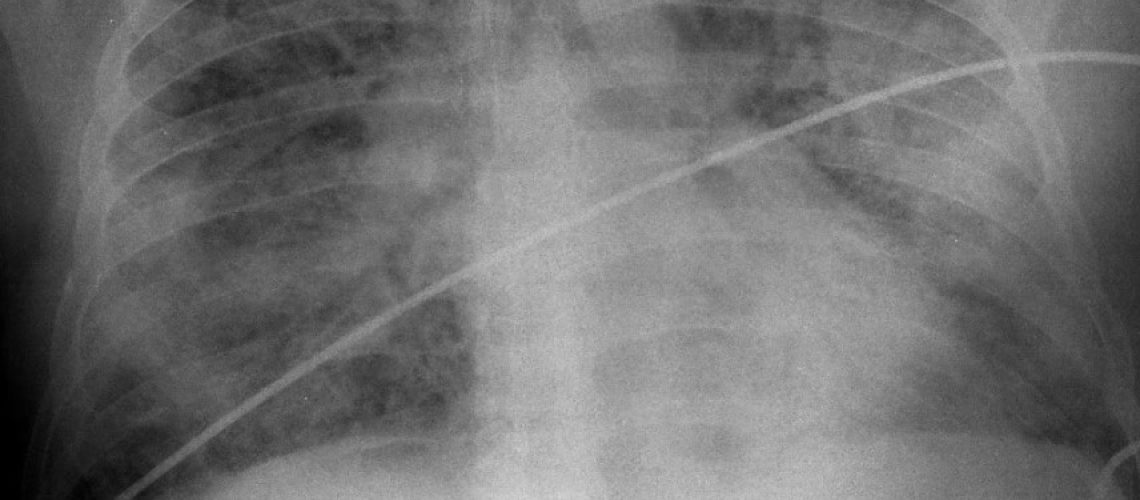

La neumonía es una infección del pulmón que puede ser causada por diferentes gérmenes como bacterias, virus y hongos. Es la infección que con mayor frecuencia justifica el ingreso de un paciente en el hospital y la causa mas frecuente de muerte de origen infeccioso.  Se clasifican según se adquieren en el ámbito extrahospitalario (neumonía adquirida en la comunidad) u hospitalario (neumonía intrahospitalaria o nosocomial). En personas sanas la neumonía está producida con mayor frecuencia por una bacteria llamada neumococo (strepectococcus pneumoniae) para la que existe una vacuna.  El tratamiento con antibióticos adecuados suele ser eficaz en la mayoría de los pacientes.